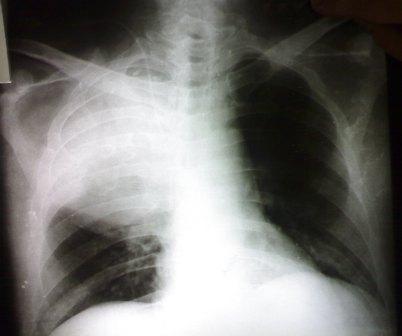

This photo is for a patient, with

chronic renal failure and on regular hemodialysis, presented with fever

and constitutional symptoms.

The well-circumscribed pattern of the lesion encouraged us to try

aspiration that revealed frank pus, so the first impression was with the

diagnosis of encysted empyema, particularly that our patient is with

chronic failure and on disalysis.

But if you meticulously re-check the photo especially the plain X-ray;

you can see an area of increased density adjacent to the trachea that

may reflect an underlying mass, so bronchoscopy was done to reveal a

mass at the right upper bronchus.

The histopathological examination of the obtained biopsies revealed

"sqaumous cell carcinoma".